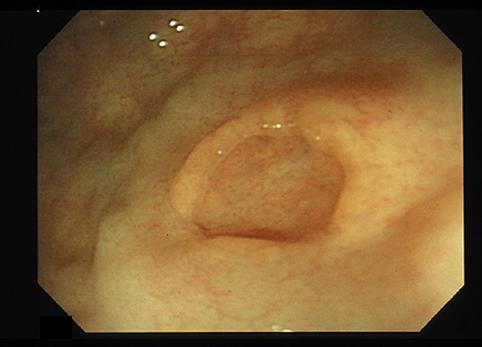

疾病(病理主体)的分类肿瘤样病变/异位粘膜

部位(按器官分)大肠/直肠

检查方法内窥镜

肿瘤最大直径10~14